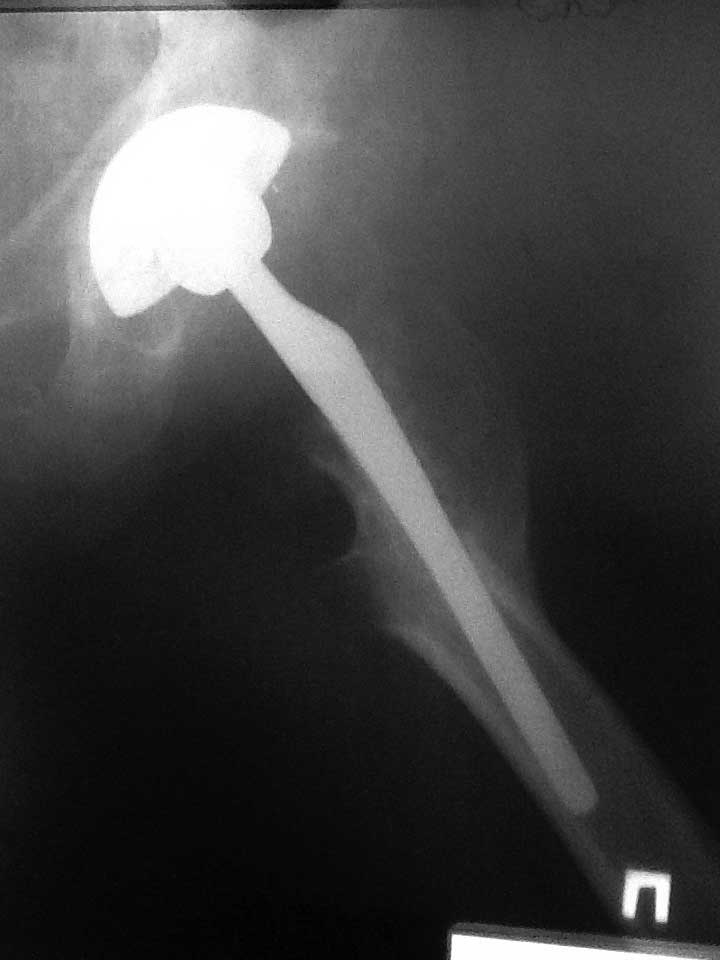

Уважаемые коллеги помогите определиться с тактикой Пациент 60-ти лет около двух лет назад выполнено тотальное б/цементное эндопротезирование по поводу двухстроннего коксартроза, состояния после остеотомий проксимальных отделов бедренных костей. Послеоперационный период спокойный. Больной появлялся на контрольные осмотры в 2, 6, 12 мес, 2 года. На протяжении всего времени отмечает выраженный болевой синдром в области оперированного бедра, передвигается при помощи костылей. Обследован у невролога, уровень С реактивного протеина и лейкоформула в пределах нормы, отечности на бедре нет. Учитывая измененный проксимальный отдел бедра и как следствие интраоперационные трудности обращает на себя внимание передне-заднее расположение ножки эндопротеза (конфликт с задним кортикалом) Может ли такое положение компонента быть причиной болевого синдрома? Поможет ли ревизионное вмешательство по удалению ножки и корректная установка компонента?

Это разве прямая проекция?

Прямая проекция

Уважаемый Игорь, Р-граммы не очень качественные, но если исключить неврологию, тенопатию (а это достаточно четкая клиническая картина), то складывается впечатление о нестабильности бедренного компонента. Само положение спереди назад с упором в кортикал не критично, в этом случае беспокоят боли в бедре после физической нагрузки, кость реагирует периостальным утолщением и по мере компенсаторного увеличения костной массы боль уменьшается. Но в Вашем случае смущает плохое заполнение канала в проекции дистальной части ножки на АР рентгенограммах, фиксация только на уровне остеотомии, а этого может быть недостаточно. И вообще непонятно, насколько хорошо ножка фиксирована в проксимальной части. Целесообразно сделать полипозиционные снимки. Болевой синдром столь длительной продолжительности при отсутствии других причин служит основанием для ревизии с установкой конической ножки типа Вагнера с четкой ориентацией по каналу.